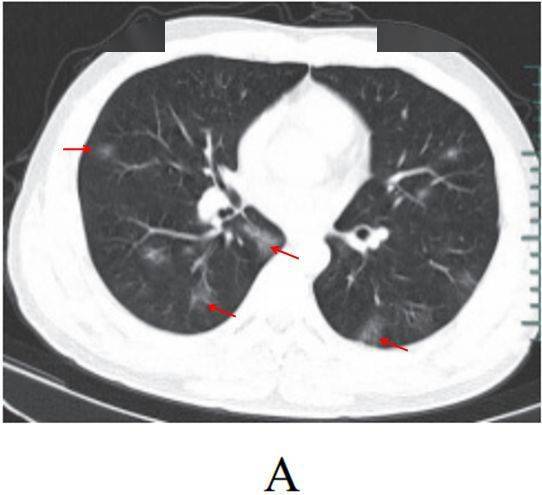

病灶形态以三种类型为主,即多叶多灶分布病灶(图 2-2A) 、单叶片状病灶(图 2-2B)和孤立性类圆形病灶(图 2-2C)

多叶多灶分布病灶(图 2-2A)